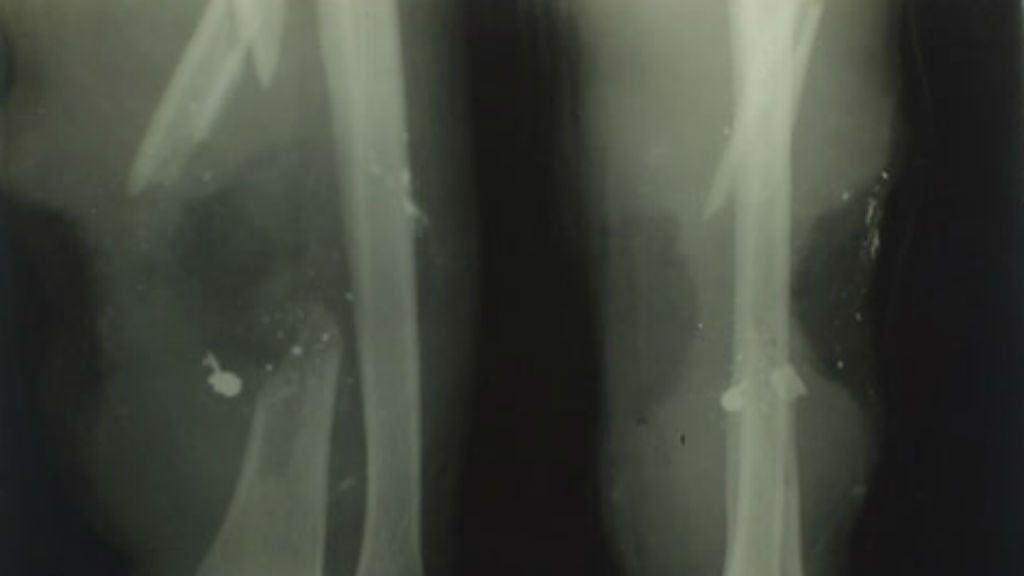

Private Hori Woolgan Jarvis of the 11th Royal West Kent Regiment had his arm shattered by a German sniper’s bullet on 14 June 1917. Many wounded soldiers with such severe injuries and shrapnel would have lost limbs through amputation but Private Jarvis was fortunate to be treated at Tunbridge Wells General Hospital. Here he was treated by the most cutting edge X-ray department outside London. Not only did X-ray make it possible for him to have a bone graft but the success of the treatment enabled him to return to his pre-war occupation as a baker and pastry chef. Sara Parker interviewed his daughter-in-law who found Private Jarvis’s original X-ray plates in the garage when her husband died. She remembers how her father-in-law had been well enough to make the wedding cake for their wedding. Sara was also shown the fragile glass X-ray plates which have been donated to Tunbridge Wells Museum and spoke to hospital archivist John Weeks about the important role of the Salomon family as benefactors. Sir David Lionel Salomon developed the X-ray department in 1915, in memory of his son, Captain David Reginald Salomons who was killed when his troop ship the HMS Hythe sunk off Gallipoli. Location: Tunbridge Wells Hospital, Kent TN2 4QJ Image: Private Hori Jarvis’ X-ray, courtesy of Liz Douglas from Tunbridge Wells Museum